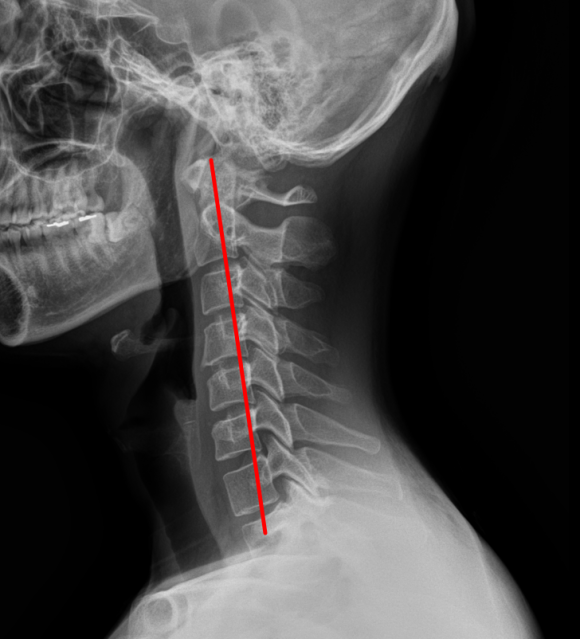

경추 X-ray

일자목 & 디스크 팽륜